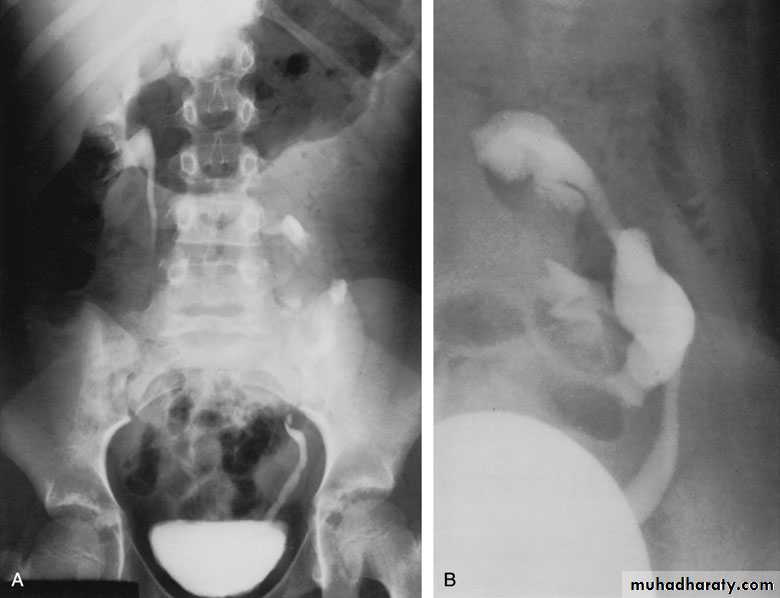

Crossed Renal Ectopia With and Without FusionHorseshoe Kidney

found in 1:1000 necropsies an is commoner in men.probably the most common of all renal fusion anomalies

The anomaly consists of two distinct renal masses lying

vertically on either side of the midline and connected at

their respective lower poles by a parenchymatous or fibrous

isthmus that crosses the midplane of the body.

Fusion of the renal masses early in embryonic life, so its ascent

will be impeded by inferior mesenteric artery.

The kidneys are low located, mal rotated and pelves lie anteriorly

Symptom When present, they are related to complications like hydronephrosis, infection, or calculus formation

Diagnosis ultrasound, IVU, CT scan